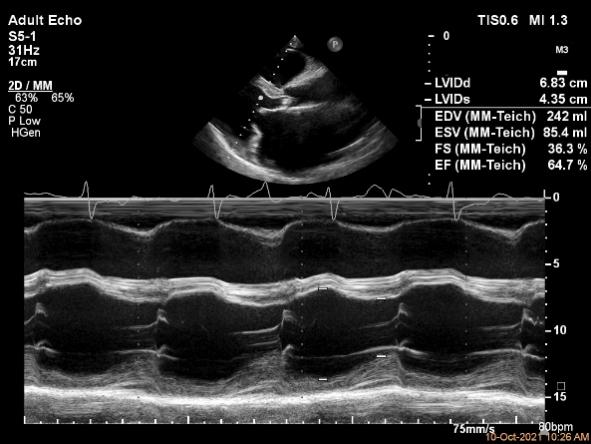

基本情况:77岁女性,患者主因发现二尖瓣反流10余年,喘憋2月入院,患者10余年前于外院体检时发现二尖瓣关闭不全(中度),无喘憋、胸闷等不适,未诊治。2月前出现夜间阵发性呼吸困难,伴双下肢水肿,至当地医院性超声心动图提示:左房77×99×118mm,左室舒张末期内径65mm,EF:55%,二尖瓣前叶收缩时部分脱向左房内,致瓣叶重度关闭不全,诊断为“二尖瓣重度关闭,心脏扩大,心力衰竭”,予规律药物治疗后,上述症状有所改善,但仍间断出现活动后胸闷、气短症状,为进一步诊治收入院。

术前超声评估结果

术前超声诊断